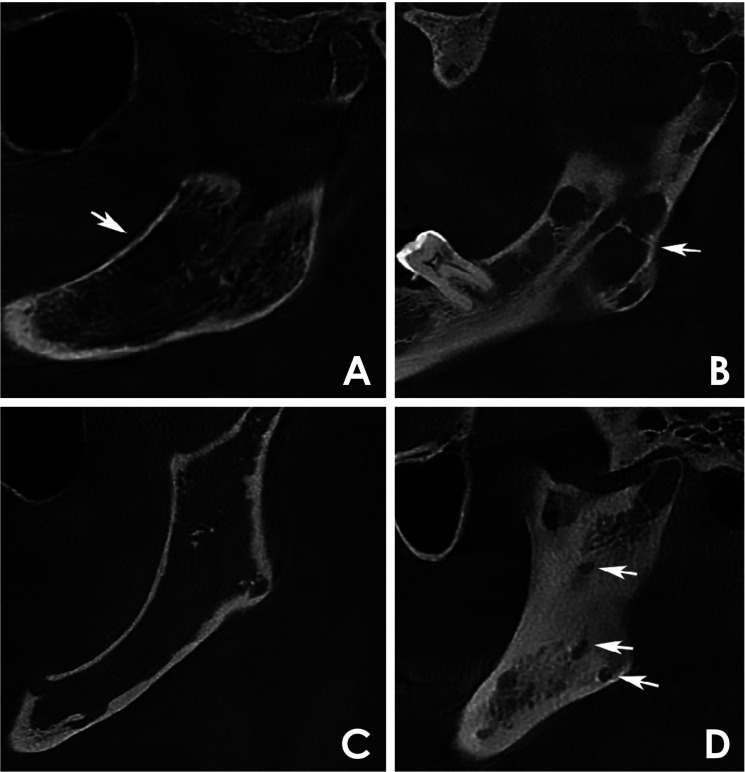

目的:本研究分析了27例多发性骨髓瘤患者在不同疾病阶段的锥形束计算机断层图像,以确定颌骨破坏模式并评估其与临床数据的关系。材料和方法:在这项横断面研究中,2名训练有素的审查员进行了标准化的、基于共识的图像分析。病变分为4种不同的骨破坏模式:弥漫性、多房性、单房性和穿孔性。临床数据从医疗记录中收集。结果:本组患者男性占51.8%,女性占48.2%,年龄以42 ~ 60岁为主。所有病例均表现为双颌弥漫性骨破坏。多房型和单房型分别占51.9%和29.6%,未发现穿孔病变。单眼模式与国际分期系统I期和Durie-Salmon期IIIA期的病例有显著相关性。结论:在研究的多发性骨髓瘤病例中,最常见的骨破坏类型是弥漫性和多房性。没有穿孔病变可能是由于使用了三维成像。在单眼模式和疾病分期之间确定了明确的关联。

Purpose: This study analyzed cone-beam computed tomography images of 27 patients with multiple myeloma at different disease stages to identify jawbone destruction patterns and assess their associations with clinical data.

Materials and methods: In this cross-sectional study, 2 trained examiners performed standardized, consensus-based image analyses. Lesions were classified into 4 distinct bone destruction patterns: diffuse, multilocular, unilocular, and punched-out. Clinical data were collected from medical records.

Results: The sample included 51.8% male and 48.2% female patients, predominantly between 42 and 60 years old. All cases exhibited diffuse bone destruction affecting both jaws. Multilocular and unilocular patterns were observed in 51.9% and 29.6% of cases, respectively, while no punched-out lesions were identified. The unilocular pattern was significantly associated with cases classified as International Staging System stage I and Durie-Salmon stage IIIA.

Conclusion: Among the studied cases of multiple myeloma, the most frequently observed bone destruction patterns were diffuse and multilocular. The absence of punched-out lesions may be attributable to the use of 3-dimensional imaging. A clear association was identified between the unilocular pattern and disease staging.